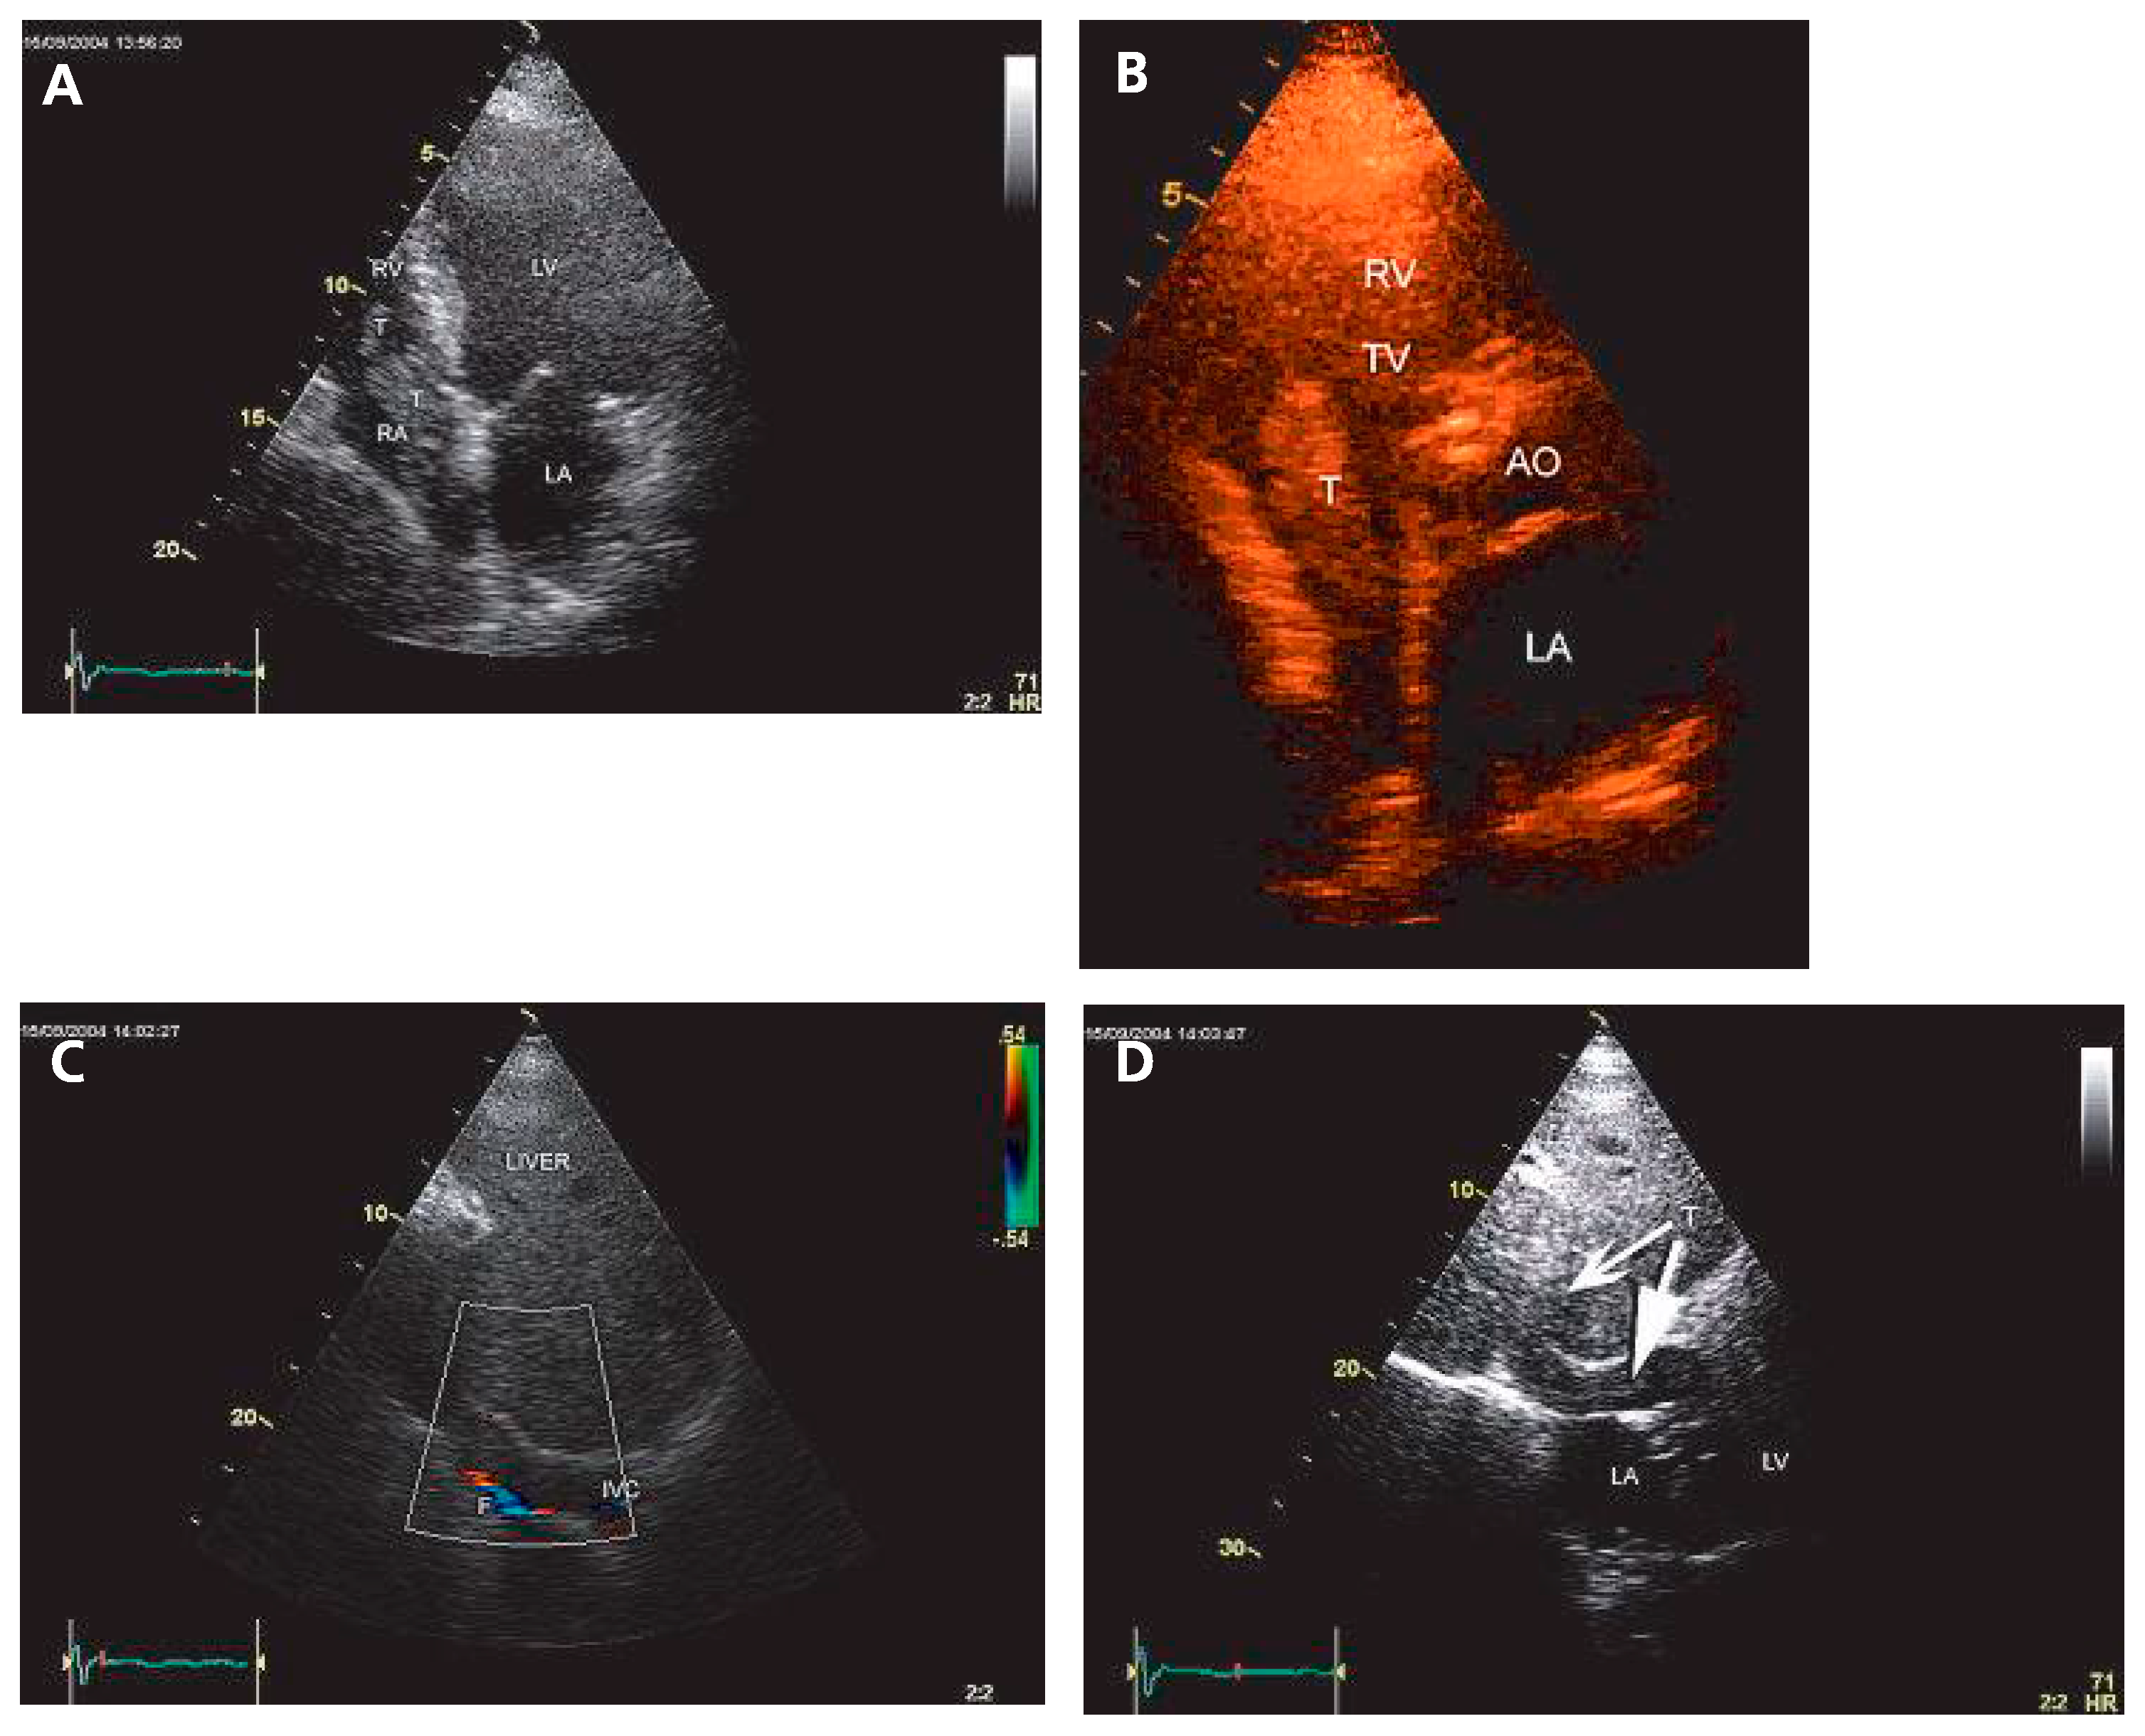

The examination unexpectedly revealed a mobile mass in the right atrium (RA) seeming to grow out of the inferior vena cava (IVC) (Figure 1A–C) and a large hepatic mass (Figure 1D).

Figure 1. TTE. (A) Apical 4-chamber-view: mobile right atrial mass (T) growing from the inferior vena cava (IVC) and prolabing into the right ventricle. (B) Slight oblique parasternal short axis showing the prolabing right atrial mass (T). (C) Color Doppler of IVC in a subcostal view showing a narrowed venous flow (F). (D) Large hepatic mass visible in the subcostal view (arrows). AO = aorta; IVC = inferior vena cava; LA = left atrium; LV = left ventricle; RV = right ventricle; RA = right atrium; TV = tricuspid valve.